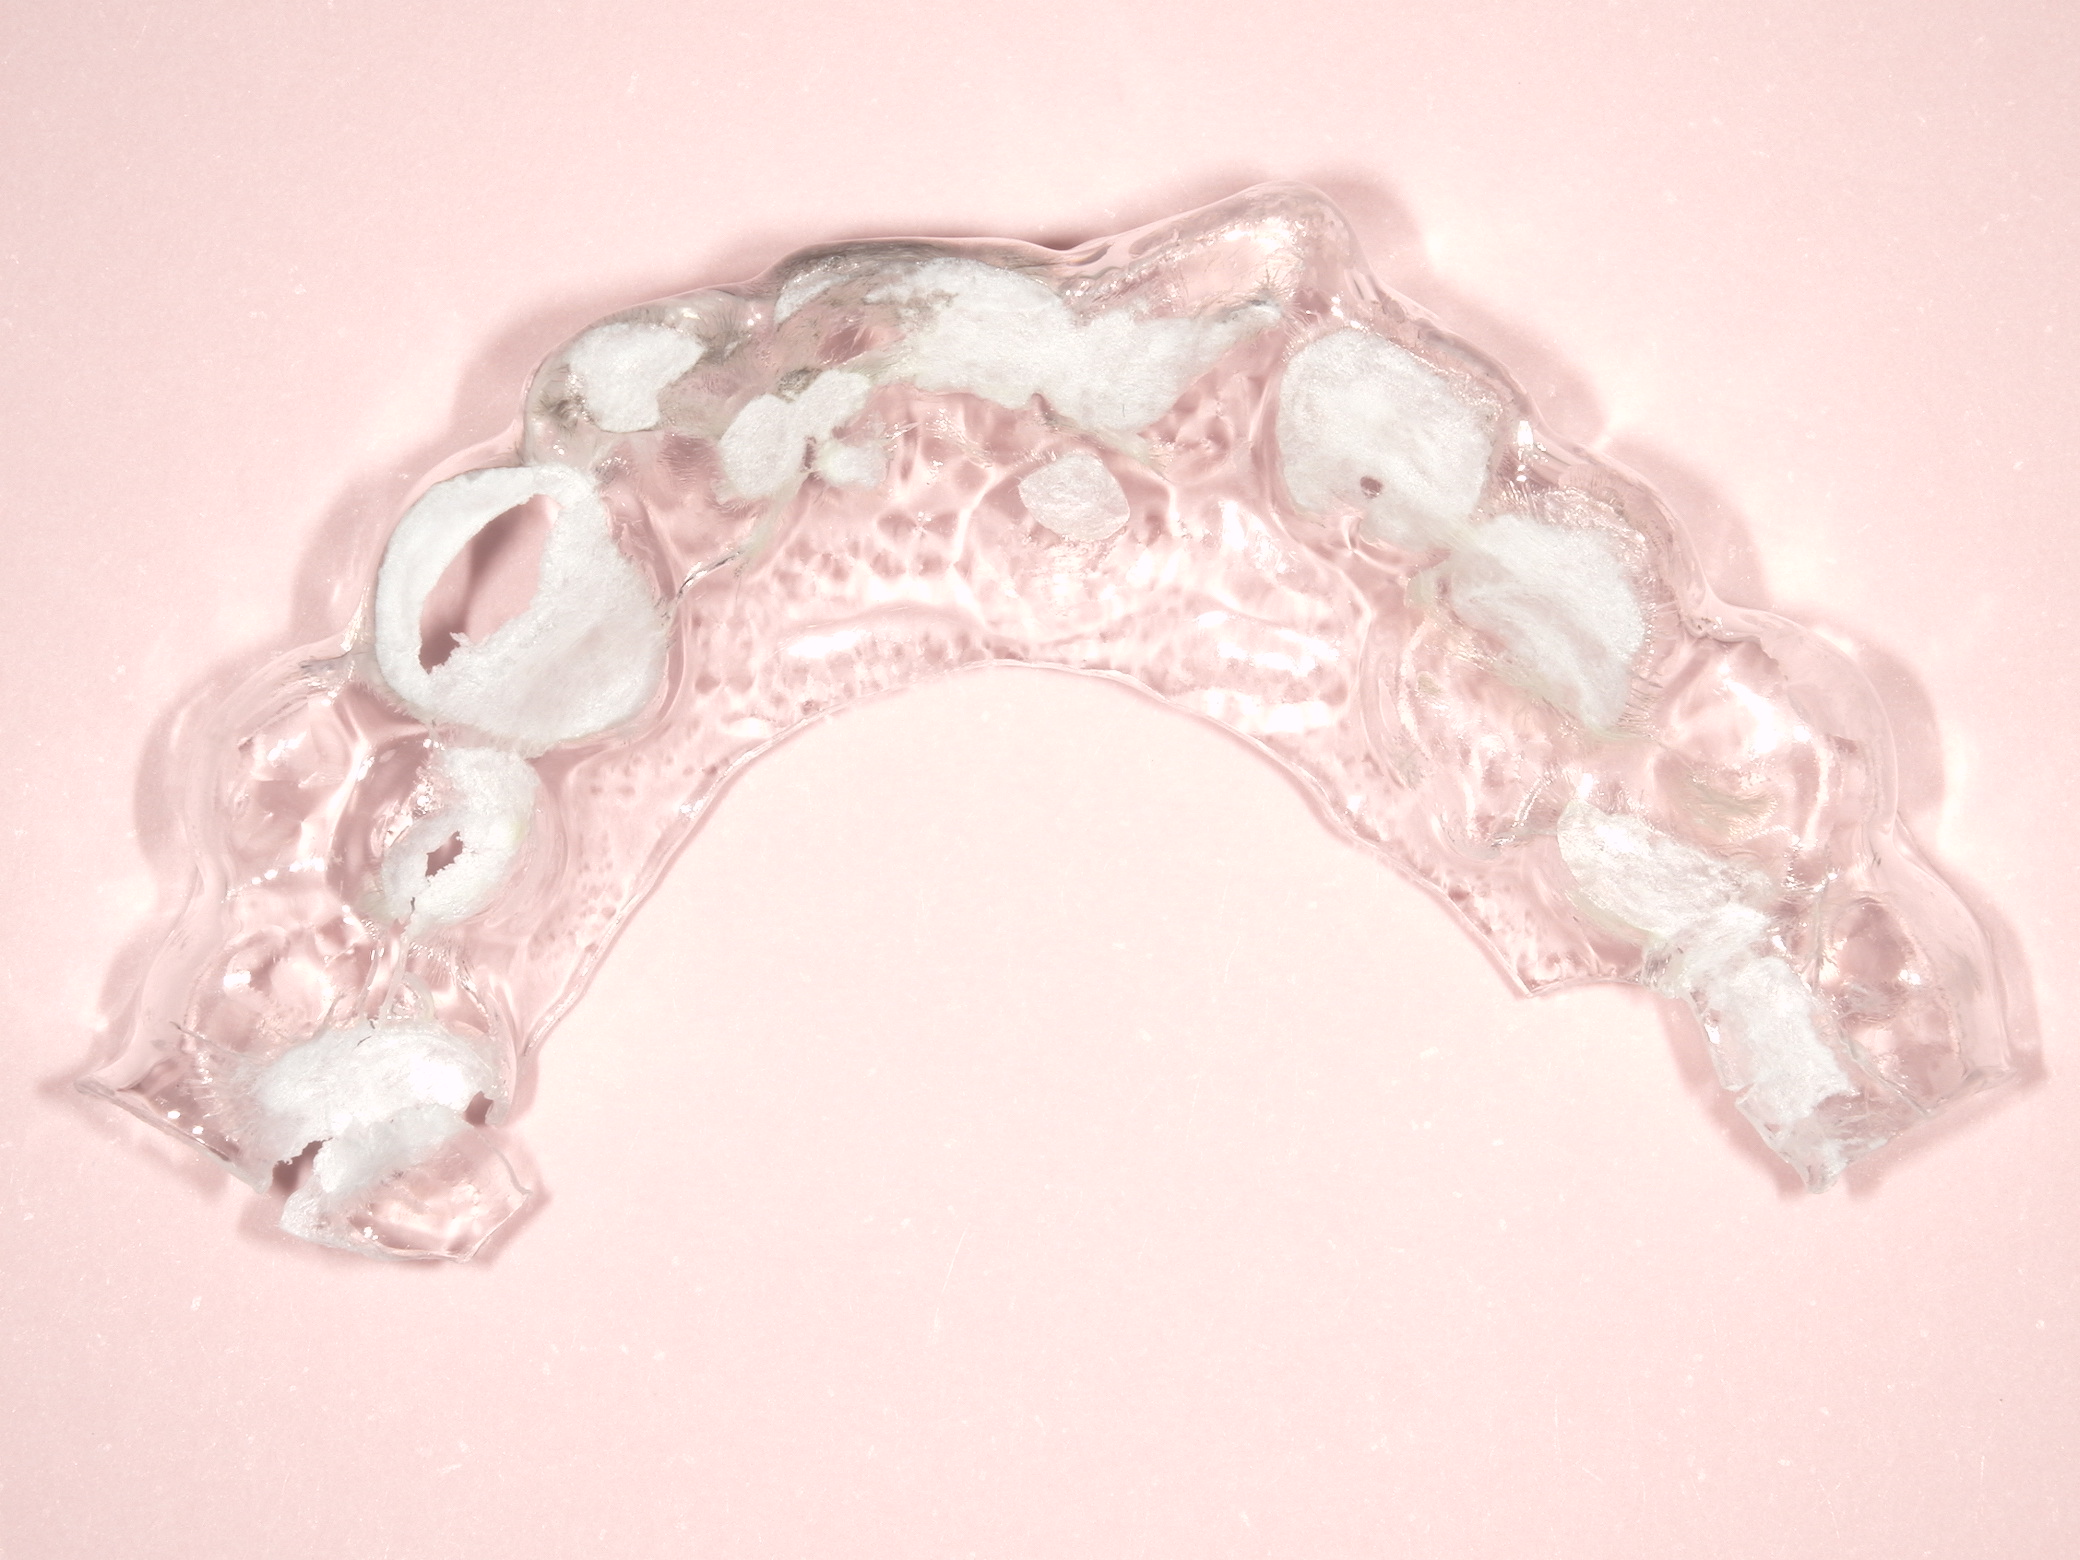

写真はナイトガードが破損したので新製の為に来院されたので写真を撮らせてもらいました。

ナイトガードは左上の3,4番部分に穴が開いていないので使えそうに見えます。が、維持力が弱く直ぐ外れてしまうので使えません。

写真のタイプのナイトガードの製作で大切な事は、できるだけ薄く作ることです。厚くなると歯が締め付けられる感じがあります。